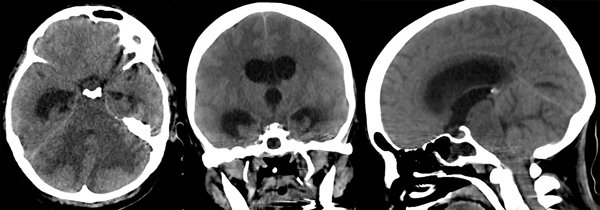

Se trata de una mujer de 47 años, portadora de angeítis de Wegener con compromiso pulmonar severo y otras comorbilidades, que requirió asistencia ventilatoria mecánica (AVM) por insuficiencia ventilatoria y posteriormente traqueostomía. Luego de varios días en AVM desarrolló en el transcurso de pocas horas estupor y deterioro de la respuesta motriz; la TC de encéfalo sin contraste mostró hidrocefalia aguda obstructiva por lesión de fosa posterior (Figura 6).

Figura 6: Tomografía computada del encéfalo donde se aprecia edema cerebeloso con compresión del tronco cerebral e hidrocefalia supratentorial aguda.

Ante la posibilidad de compromiso simultáneo irreversible del tronco cerebral se planteó la necesidad de RMN para definir la conducta a seguir, pero en menos de media hora de realizada la tomografía la paciente desarrolló pupilas intermedias no reactivas a la luz. Se realizó entonces la evacuación inmediata de 25 ml de LCR por vía transorbitaria derecha (Figura 7), recuperándose instantáneamente el reflejo fotomotor.

Figura 7: Punción ventricular transorbitaria derecha. Se aprecia la salida de LCR por la aguja. La profundidad alcanzada por la misma fue de 6 cm. La paciente estaba traqueostomizada por su patología pulmonar.